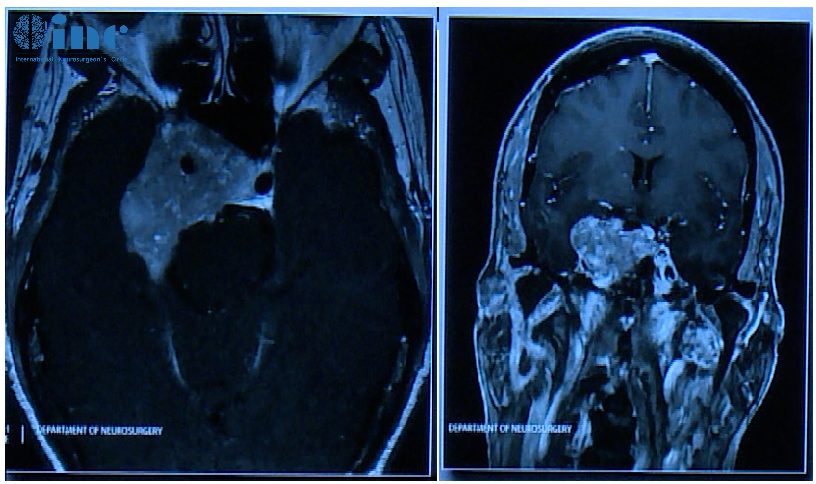

患者术前情况:62岁女性,患者35年前有垂体大腺瘤复发史,随后接受放射治疗复发性肿瘤引起的侧性眼球麻痹的进行性复视。

术后影像片子显示肿瘤切除干净:

术前影像显示肿瘤较大:

术后影像,肿瘤体积明显缩小

治疗部分二:右额开颅术经皮质入路治疗颅内残余肿瘤

术后影像: